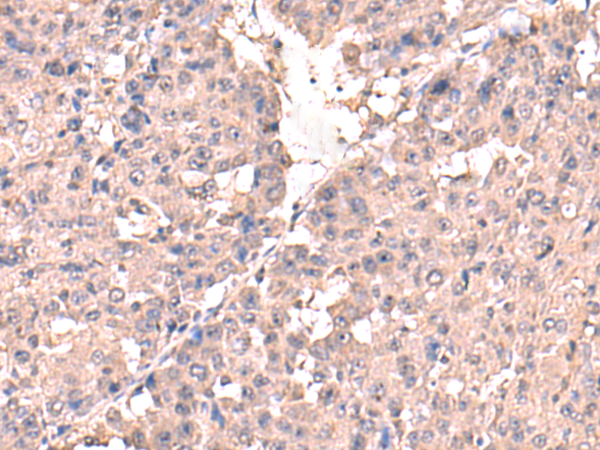

IHC positive control: |

Human liver cancer |

IHC Recommend dilution: |

50-300 |